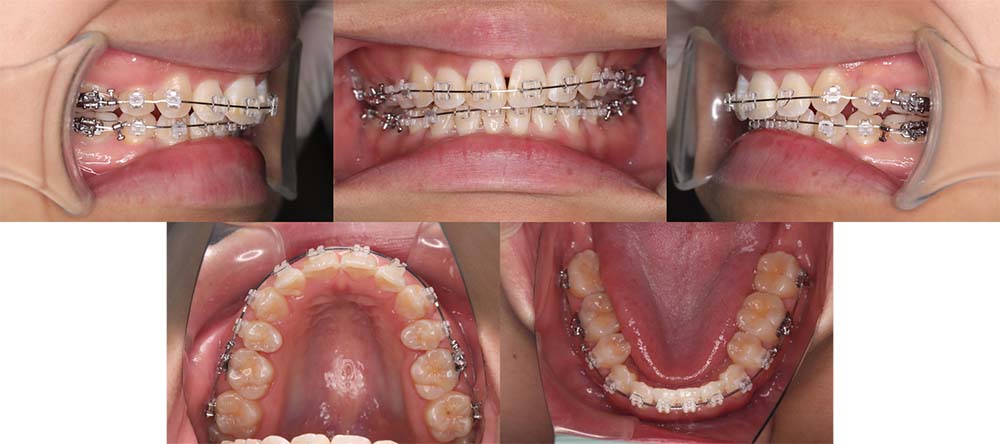

| 症例分類 | 顎変形症、叢生、側方偏移 |

| 診断名 | 下顎右側偏移を伴う上下叢生 |

| 主訴 | 歯並びがガタガタ、顎が右にずれている |

|---|---|

| 年齢 | 25歳4ヶ月 |

| 性別 | 女性 |

| 抜歯部位 | 上の左右第一小臼歯 |

| 使用装置 | 表側のワイヤー装置+外科矯正(手術を併用した治療) |

| 治療期間 | 2年1ヶ月 |

| 保定装置 | 固定式保定装置、取り外し式保定装置(8時間) |

| 費用 |

保険適応 [検査・診断等] 2万円程度 [装置装着] 5〜7万円程度 [調整料] 2,000〜7,000円程度/回 [手術前検査等] 2万円程度 [保定装置等] 4万円程度 合計18〜25万円程度 |

下顎の右側に偏移があり、骨格的にも受け口だったため、上顎両側第一小臼歯を抜去して、上下顎の手術を併用して治療を行いました。術前は前歯が反対のかみ合わせになり、初診時より咬合、顔貌は一旦悪くなります。術前矯正を1年7ヶ月した後に手術を行いました。

術後の顎間ゴムをしっかりと使用していただけたため、術後7ヶ月で治療が終了することができました。また、顎の歪みが残っていたため矯正治療終了後におとがい形成術をして、下顎の偏移を改善しました。

顎の歪みも下顎の前方感も改善することができ、上下のかみ合わせもしっかりと咬合することができました。